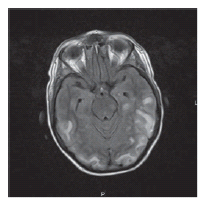

Within days of admission, her mental status declined requiring initiation of mechanical ventilation. The patient remained febrile during her hospital course (> 7 days) and eventually became hemodynamically unstable and developed a shock state requiring multiple vasopressor agents. A magnetic resonance image of the brain (Figure 1) demonstrated areas of subcortical T2 signal abnormality involving the posterior temporal, parietal, and occipital lobes. Cerebral spinal fluid analysis revealed clear, colorless fluid with 2 red blood cells/µL and no white blood cell count, with an elevated glucose of 6.27 mmol/L, and protein of 6.2 g/L. Cerebral spinal fluid cultures, blood cultures, and urine cultures were negative for bacterial, acid-fast bacteria, fungal, and viral infections. Cerebral spinal fluid was also negative for Epstein-Barr virus DNA, enterovirus RNA, JC virus DNA, varicella-zoster virus DNA, West Nile virus DNA, and herpes simplex virus DNA. Further blood work-up included Epstein-Barr virus, parvovirus B19, herpes simplex virus, human herpesvirus 6, human herpesvirus 8, and cytomegalovirus, all negative by polymerase chain reaction analysis for DNA. An electroencephalogram was performed, finding multifocal and independent epileptiform discharges independently over both hemispheres with moderate bihemispheric slow-wave activity.

Figure 1. Subcortical T2 signal abnormality involving the posterior temporal, parietal and occipital lobes.